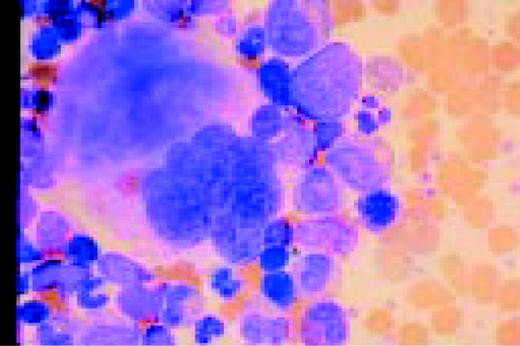

Slide L39

Multiple myeloma, bone marrow aspirate. Virtually every cell in the field is a neoplastic plasma cell. They show nuclear eccentricity, pleomorphism, and a tendency to stick together in clumps.FIG39